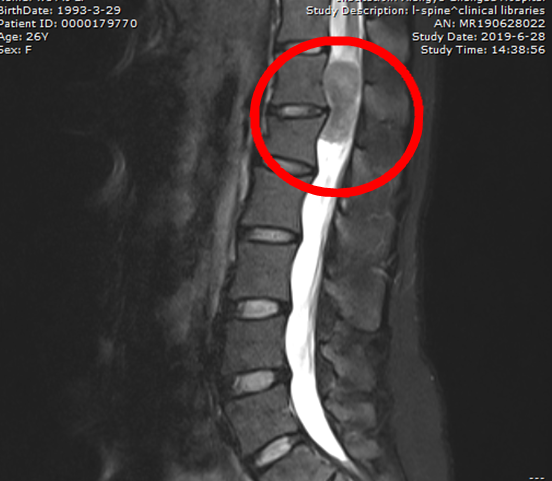

患者术前CT图

据骨科张丕胜教授称,根据伍女士临床表现及影像学检查所见,其腰腿痛的罪魁祸首便是椎管内长达7cm的肿瘤,其肿瘤占位甚至达到80%。也就是说,椎管内的肿瘤已经对脊髓及马尾神经造成了严重的压迫,其危害是难以想象的,如果诊治不及时,后期可能出现大小便失禁,甚至造成下肢瘫痪。伍女士怎么也没有想到,这颗“隐形炸弹”除了给自己带来了无限的痛苦,竟还有如此大的隐患。